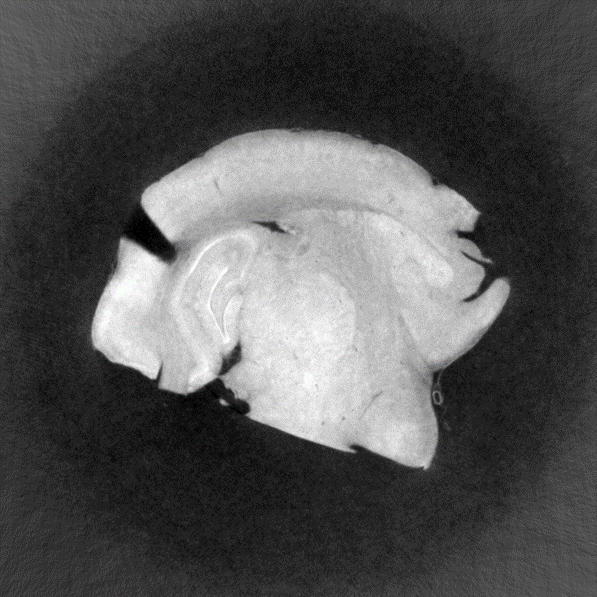

マウス脳

屈折コントラスト法(DEI)

17.8 keV

75分

試料提供:北里大学Lwin准教授